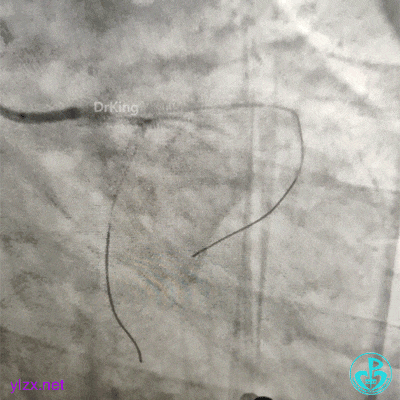

果断更换指引导管。

指引导管刚刚送到升主动脉,患者便发生抽搐、呼之不应,立即胸外按压几次后,患者清醒了,快速置入IABP。造影发现整个前壁不怎么搏动了。

植入4.0×13mm支架1枚。